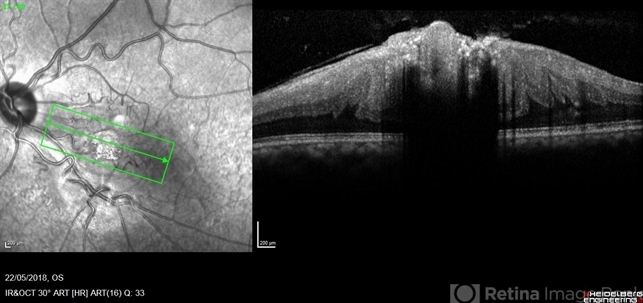

- Combined hamartoma of the retina and retinal pigment epithelium (CHRRPE)

- combined hamartoma, optical coherence tomography (OCT)

- Coupled OCT B-scan and IR imaging of a 17-year-old man with combined hamartomas of the retina and retinal pigment epithelium (CHRRPE) at the posterior pole of the left eye. One can see a highly reflective elevated macular lesion with hyporeflective shadowing of the underlying tissue and obscuration of the normal retinal layers.